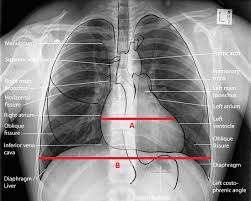

Chest X Ray To Check Fitness Is Outdated Health Gulf News

Chest X Ray To Check Fitness Is Outdated Health Gulf News from gulfnews.com